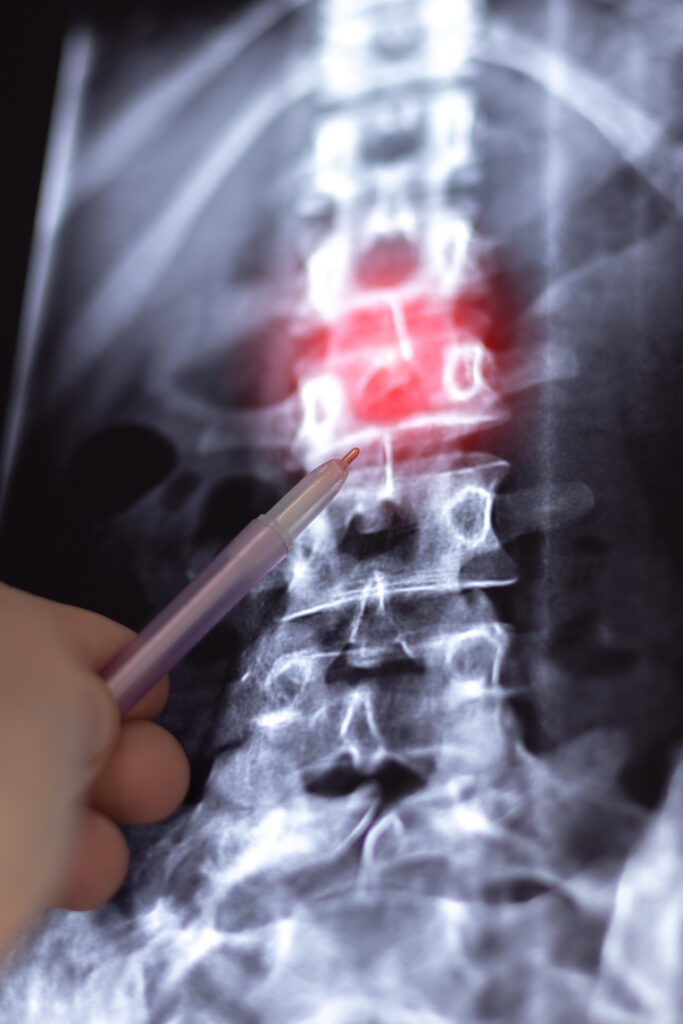

Individuals with a herniated disc often experience sharp or radiating pain in the back, neck, or limbs, along with numbness, tingling, or muscle weakness caused by nerve compression. These symptoms can make it difficult to sit for long periods, lift objects, bend, or even walk steadily — all of which directly interfere with the ability to maintain consistent employment. Treatment options typically include physical therapy, pain management injections, medications, and in more severe cases, surgical intervention to relieve pressure on the nerves. While some people improve with treatment, herniated discs do not always fully heal and may lead to recurring or chronic issues. For many, the condition tends to worsen over time, especially with age or physical strain, making it a long-term challenge.

Understanding Herniated Discs

A herniated disc happens when the cushioning material between vertebrae slips or ruptures, pressing on nearby nerves. This condition can lead to:

• MRI or CT scans confirming disc herniation